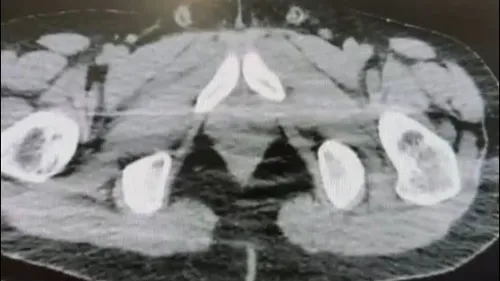

Nevşehir'de düzenlenen operasyonda midelerinde uyuşturucu sevkiyatı yaptığı belirlenen S.B. ve O.R. tutuklandı; çok sayıda kapsül, uyuşturucu ve para ele geçirildi.

Nevşehir'de midelerinde uyuşturucu sevkiyatı yapan 2 şüpheli tutuklandı Nevşehir İl Emniyet Müdürlüğü Narkotik Suçlarla Mücadele Şube Müdürlüğü ekipleri tarafından gerçekleştirilen operasyonda, midelerinde uyuşturucu sevkiyatı yaptığı belirlenen iki kişi gözaltına alındı. Operasyon, Cumhuriyet Başsavcılığı koordinasyonunda yürütüldü. Operasyonun kapsamı Ekiplerin sokak satıcılarına…